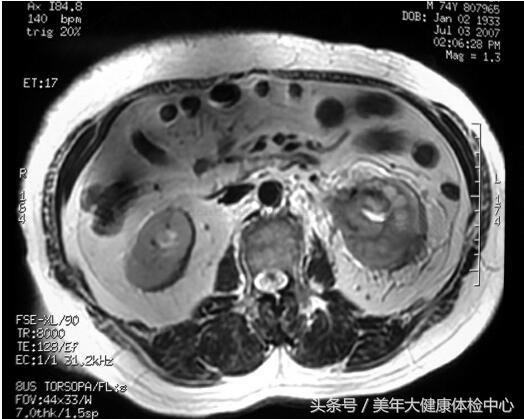

MR(图13-2):左肾盂、肾盏及肾周间隙病变,范围约4.5cm×3.5cm,形态不规则,边界不清,病变T1为等信号,T2低-等信号。动脉期有强化,实质期及延迟期增强更明显,肾周脂肪间隙见条索状强化。

图13-2 MR